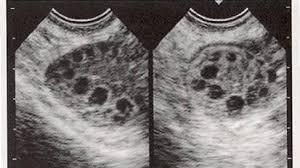

首先,什么是卵巢多囊样改变?主要指B超下,卵巢表现为一侧或者双侧内可见直径2~9mm卵泡》12个,和卵巢体积增大》10cm。

多囊卵巢综合征(PCOS)是一种由内分泌异常(高雄激素和胰岛素抵抗)导致卵泡发育和分泌异常引起的妊娠疾病。本病需根据症状、病史、实验室检查、彩色多普勒超声等进行诊断。患者可能有毛茸茸,黑棘皮病,肥胖,或多或少月经,和一个较长的周期(2个月,甚至半年)。实验室检查可发现雄激素过高、LH/ISH值异常、胰岛素抵抗等。彩色多普勒超声显示卵巢呈项链征,即卵泡排列方式与项链相同,数目多(10~12),大小较小,而不是卵泡形成。

你好,多囊卵巢综合症诊断是标准的。第一、就是月经失调、排卵障碍,多数表现月经推后(四五十天或两三个月一行),严重可能会闭经,也有少数表现为月经紊乱,稀发排卵或每个月经都不排卵。第二、高雄激素的表现,体毛多、痤疮等,或者查出性激素雄激素偏高。第三、妇科B超显示呈多囊样改变。即一侧或两侧卵巢内小卵泡的数目等于大于12个。在排除其它疾病所致的稀发或无排卵或其它疾病所致多囊卵巢,在上面三条里面具备了两条就可以下一个多囊卵巢综合征的诊断。

而多囊卵巢综合征是对怀孕有影响,这是一种内分泌异常(雄激素过高,胰岛素抵抗)导致卵泡发育及分泌异常导致的疾病。该病需要根据症状、病史、化验室检查、彩超检查等综合诊断。该病的患者可能会出现多毛、黑棘皮症、肥胖、月经量多或量少、周期较长(2个月甚至半年)等症状。化验室检查会发现雄激素过高,LH/FSH值异常、胰岛素抵抗等。彩超下见卵巢是呈项链征,即是卵泡呈项链一样排列,数目较多(10到12个),大小较小,未有又是卵泡的形成。